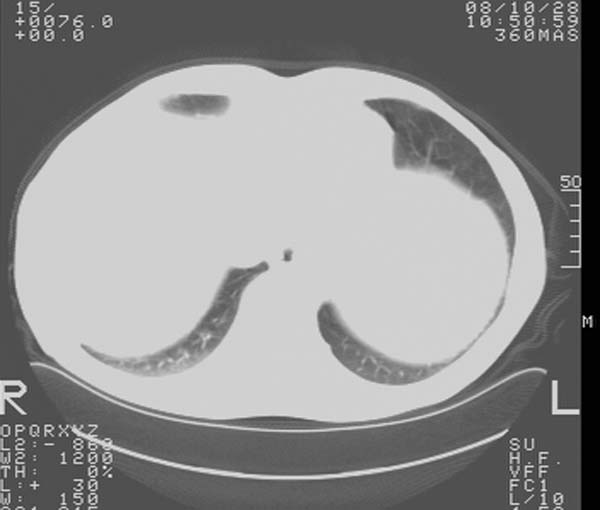

m,65y。半年前发现颈小结节,逐渐增多增大,现双侧耳后、颌下及颈部表浅淋巴肿大。胸片示双肺门增大。外院曾穿刺诊断为淋巴结核。在我科作胸腹部ct,我们觉得外院病检有误。现将图像上传请战友讨论。

纵隔内及腹膜后广泛淋巴结肿大,脾大,肝内似可见低密度影,结合病史半年前发现颈小结节,逐渐增多增大,现双侧耳后、颌下及颈部表浅淋巴肿大。考虑淋巴瘤。

我们也是首先考虑淋巴瘤。只是外院病检报告是结核。让人迷惑。肝左叶多发低密度占位,没增强不好定论。

纵隔,双肺门腹膜后多发淋巴结重大,非融合,肝脾轻度肿大,双肺野弥漫性小结节;考虑淋巴瘤,结节病可能性

纵隔内,双肺门、腋窝及腹膜后多发肿大淋巴结影,肺内小结节影,肝脾体积增大,支持淋巴瘤。肝内多发低密度影,考虑小囊肿。